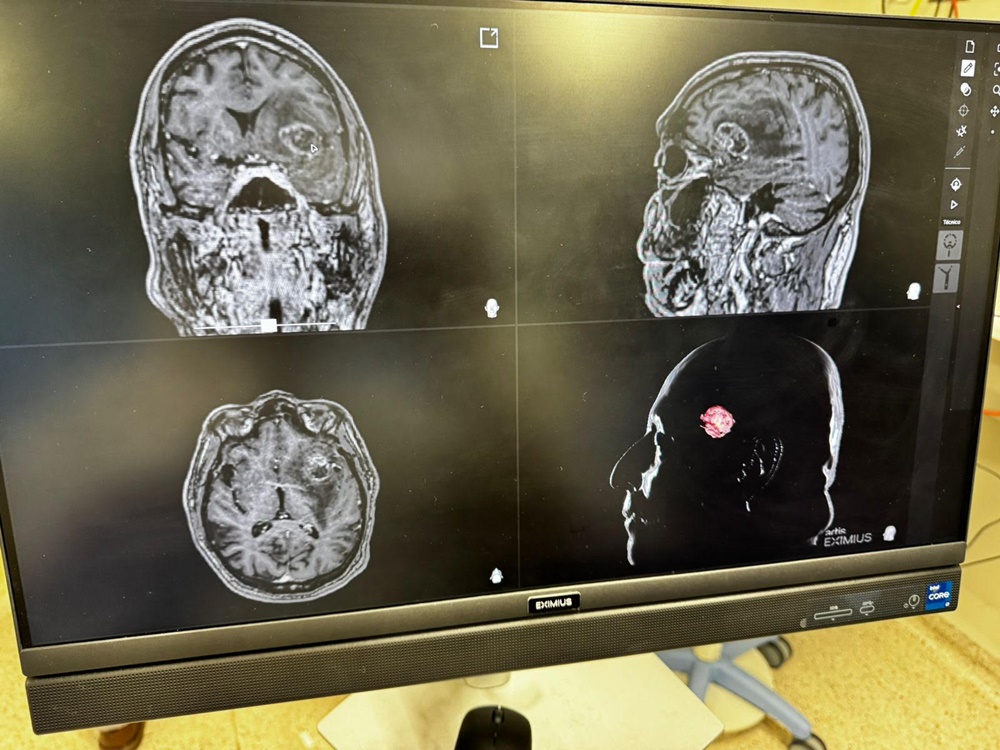

Essa precisão é reforçada pelo uso da neuronevegação, uma tecnologia de ponta disponível na Cassems que funciona como um GPS intracraniano. Através de uma ponteira laser, o médico consegue localizar a lesão com exatidão milimétrica na ressonância em tempo real. “Isso diminui muito o quanto a gente manipula o cérebro, agindo apenas na área estritamente necessária”, pontua Zanin.